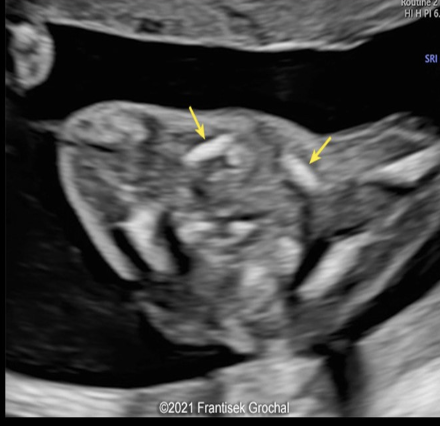

trisomy 13 is suspected

a) A

b) B

c) C

d) D